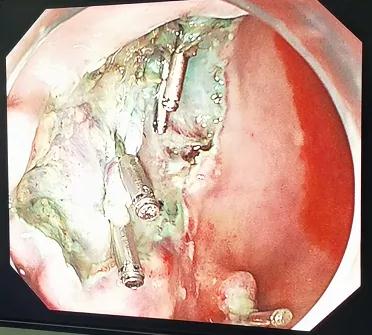

因患者胃“息肉”数目较多,且其中部分不排除局灶早期癌变可能,在充分评估患者情况基础上考虑做放大染色胃镜精查准备。在麻醉科密切配合下,借助高清放大染色胃镜,我们观察到几枚“息肉”相互邻近,同时发现了普通白光胃镜不易察觉的浅隆起病灶,存在可疑早癌征象,与患者家属充分沟通后,省立医院专家指导下,适当扩大切除范围,改行经胃镜胃粘膜下层剥离术(ESD)。操作非常顺利,成功切除了可疑病灶。该病人术后恢复良好,正在随访中。